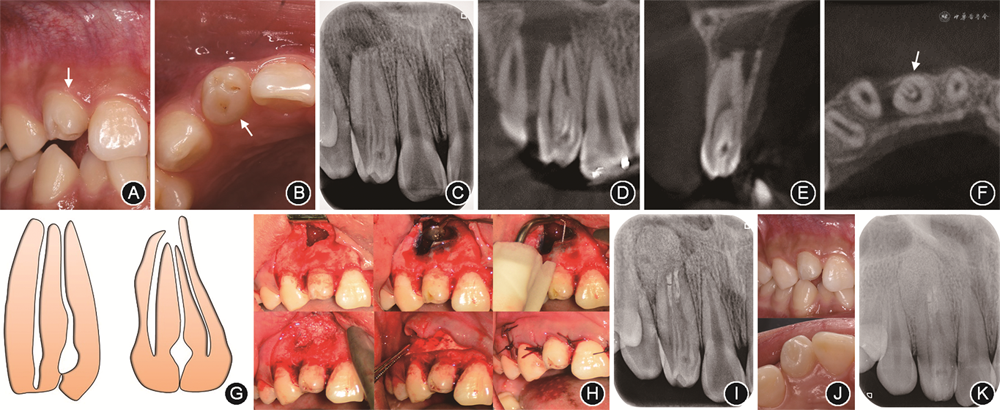

患者男性,17岁,2019年8月因“右上前牙变色半年,牙龈脓包并胀痛1个月”就诊于某口腔诊所,开髓后因“根管形态复杂”转诊至中南大学湘雅口腔医学院·口腔医院牙体牙髓科。就诊时患牙胀痛缓解,轻微咬合痛,无冷热刺激痛,无夜间痛。患者既往体健,否认全身系统性疾病史及传染病史,无药物过敏史,无牙外伤史。

(1)临床检查:患者面型对称,张口度正常,关节无弹响,张口无偏斜。口内检查(图1A,B):前牙反

,口腔卫生良好,牙龈略红肿。12牙色偏暗,腭侧釉质内陷至根面,开髓孔开放,髓腔内有棉捻,根管无探痛,冷热测试无反应,垂直叩痛(+),水平叩痛(-),不松动。唇侧根尖区轻度肿胀,扪诊胀痛,无窦道,牙周探诊无异常。

(2)影像学检查:根尖片示12牙冠部硬组织内陷,可见多根管影及根尖周低密度影(图1C)。锥形束CT示12牙冠开髓孔,釉质内陷超过釉质牙骨质界内陷腔,未达根周膜,根尖区可见2.2 mm×7.0 mm×6.5 mm大小的根尖区低密度影,边界清晰,近中牙槽嵴吸收(图1D~F)。

(3)诊断:12慢性根尖周炎;12牙内陷(Oehlers Ⅲa型)(图1G);慢性牙龈炎。

第1次治疗:橡皮障隔离患牙,显微镜下清理髓腔(图1H),10号K锉探查近中和远中根管均通畅,电子根管测量仪测量工作长度均为25 mm(VDW,德国),内陷腔不能疏通。超声ET20(赛特力,法国)磨除内陷腔牙本质。机用镍钛锉Mtwo(VDW,德国)根管预备,主尖锉预备至35号0.04锥度,预备全程用0.5%次氯酸钠溶液冲洗根管。最后用5.25%次氯酸钠溶液、17%乙二胺四乙酸溶液、0.5%次氯酸钠溶液、无菌水5~10 ml依次超声荡洗30 s~1 min。干燥根管后使用氢氧化钙糊剂诊间封药,富士Ⅶ玻璃离子(GC,日本)暂封髓腔。

第2次治疗(首次治疗13 d后):橡皮障隔离患牙,显微镜下去除暂封材料,依次使用5.25%次氯酸钠溶液、17%乙二胺四乙酸溶液Er:YAG 激光(SSP 20 mJ,15 Hz,0.3 W)辅助荡洗根管,无菌水冲洗干燥后,Nd:YAG(MSP 15 Hz,1.5 W)根管消毒(图1I)。使用牙胶尖蘸取生物陶瓷根管封闭糊剂iRoot SP(Innovative Bio Creamix Inc,加拿大)沿根尖向上,均匀涂布根管壁;随后使用垂直加压器将生物陶瓷根管修复材料iRoot BP Plus(Innovative Bio Creamix Inc,加拿大)充填所有根管,显微镜下观察根管口充填情况(图1J),拍摄术后即刻根尖片(图1K)。髓腔内暂封吸湿棉球(Roeko,Coltene,德国)1周,iRoot BP Plus充分固化后,光固化复合树脂(Z350 XT,3M,美国)分层充填髓腔,抛光。术后3个月复查,患牙无不适,根尖片显示根尖周病变基本愈合(图1L)。